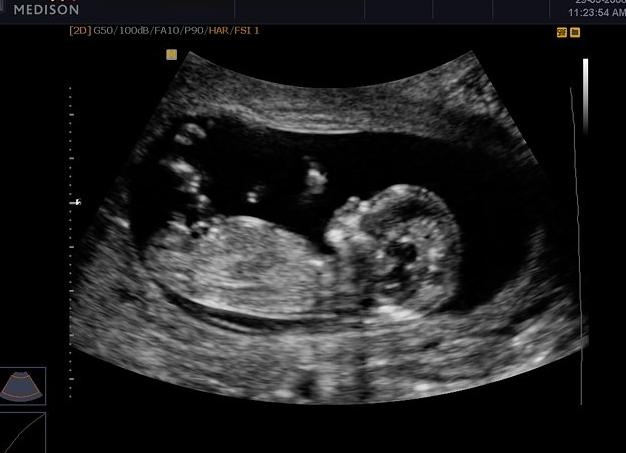

На 12 неделе плод уже практически сформирован. Именно на этом сроке проводится первое обязательное УЗИ, которое поможет определить, как протекает беременность, предупредить патологию, услышать сердцебиение и т. д. В этот период очень важно обращать внимание на КТР (копчико-теменной размер) плода, чтобы определить, как развивается малыш, и нет ли у него отклонений.

На 12 неделе беременности плод весит примерно 15 г, а рост его составляет около 7 см, это норма для плода (см. фото). Как видно, показатели, по сравнению с 11 неделей, увеличились.

12-я неделя беременности завершает период первого триместра. Величина плода в положении эмбриона достигает величины до 7 см и весом около 63 грамм.

На данном периоде у ребенка уже отчетливо просматриваются все части тела. Конечности сформировались, пальцы находятся в стадии конечного формирования – на них пока еще не появились ногти. Ребенок находится в движении. Он слышит разговоры и реагирует на них. С этого периода можно различить пол младенца и запечатлеть на фото с УЗИ на 12 неделе беременности. Такая фотография будет самым эксклюзивным из всех снимков в альбоме ребенка.

По УЗИ легко определить размер плода, который растет, ежедневно меняется, становится больше похожим на обычного человека, это отчетливо видно на фото. Общий размер составляет около шестидесяти одного миллиметра от темечка до крестца, и сравнимо с обычным куриным яйцом. Для данного срока беременности – норма.

На УЗИ можно рассмотреть ножки, ручки, пальчики, носик, послушать сердцебиение малыша. Сейчас на его пальчиках начинают расти ногти.

В 12 недель беременности фото плода покажетместо прикрепления плодного яйца в матке. К этому времени размер яйца от 57 мм, вес малыша к этому времени составляет 14–16 грамм и рост 5–7 см.

Главное, что интересует специалиста при проведении УЗИ – это, конечно, плод. Его размер в этот период сопоставим с длиной женского мизинца, частота сердечных сокращений составляет до 160 ударов в минуту, желточный мешок уже не визуализируется, формирующаяся плацента может быть прикреплена к любой из стенок или дну матки.

Как выглядит малыш

Размер ребенка от темени до копчика составляет порядка 5-6 см, что уже весьма немало, в сравнении с тем, что было ровно половину срока назад, когда величина эмбриона была всего 5-6 мм. В этот период ребенок активно растет, при исследовании его можно увидеть, как вполне симпатичного человечка с короткими ручками и ножками, что вызывает у будущих мам умиление, а у особо чувствительных из них – даже слезы. Ребенок активно двигается, машет ручками, дрыгает ножками, зевает.